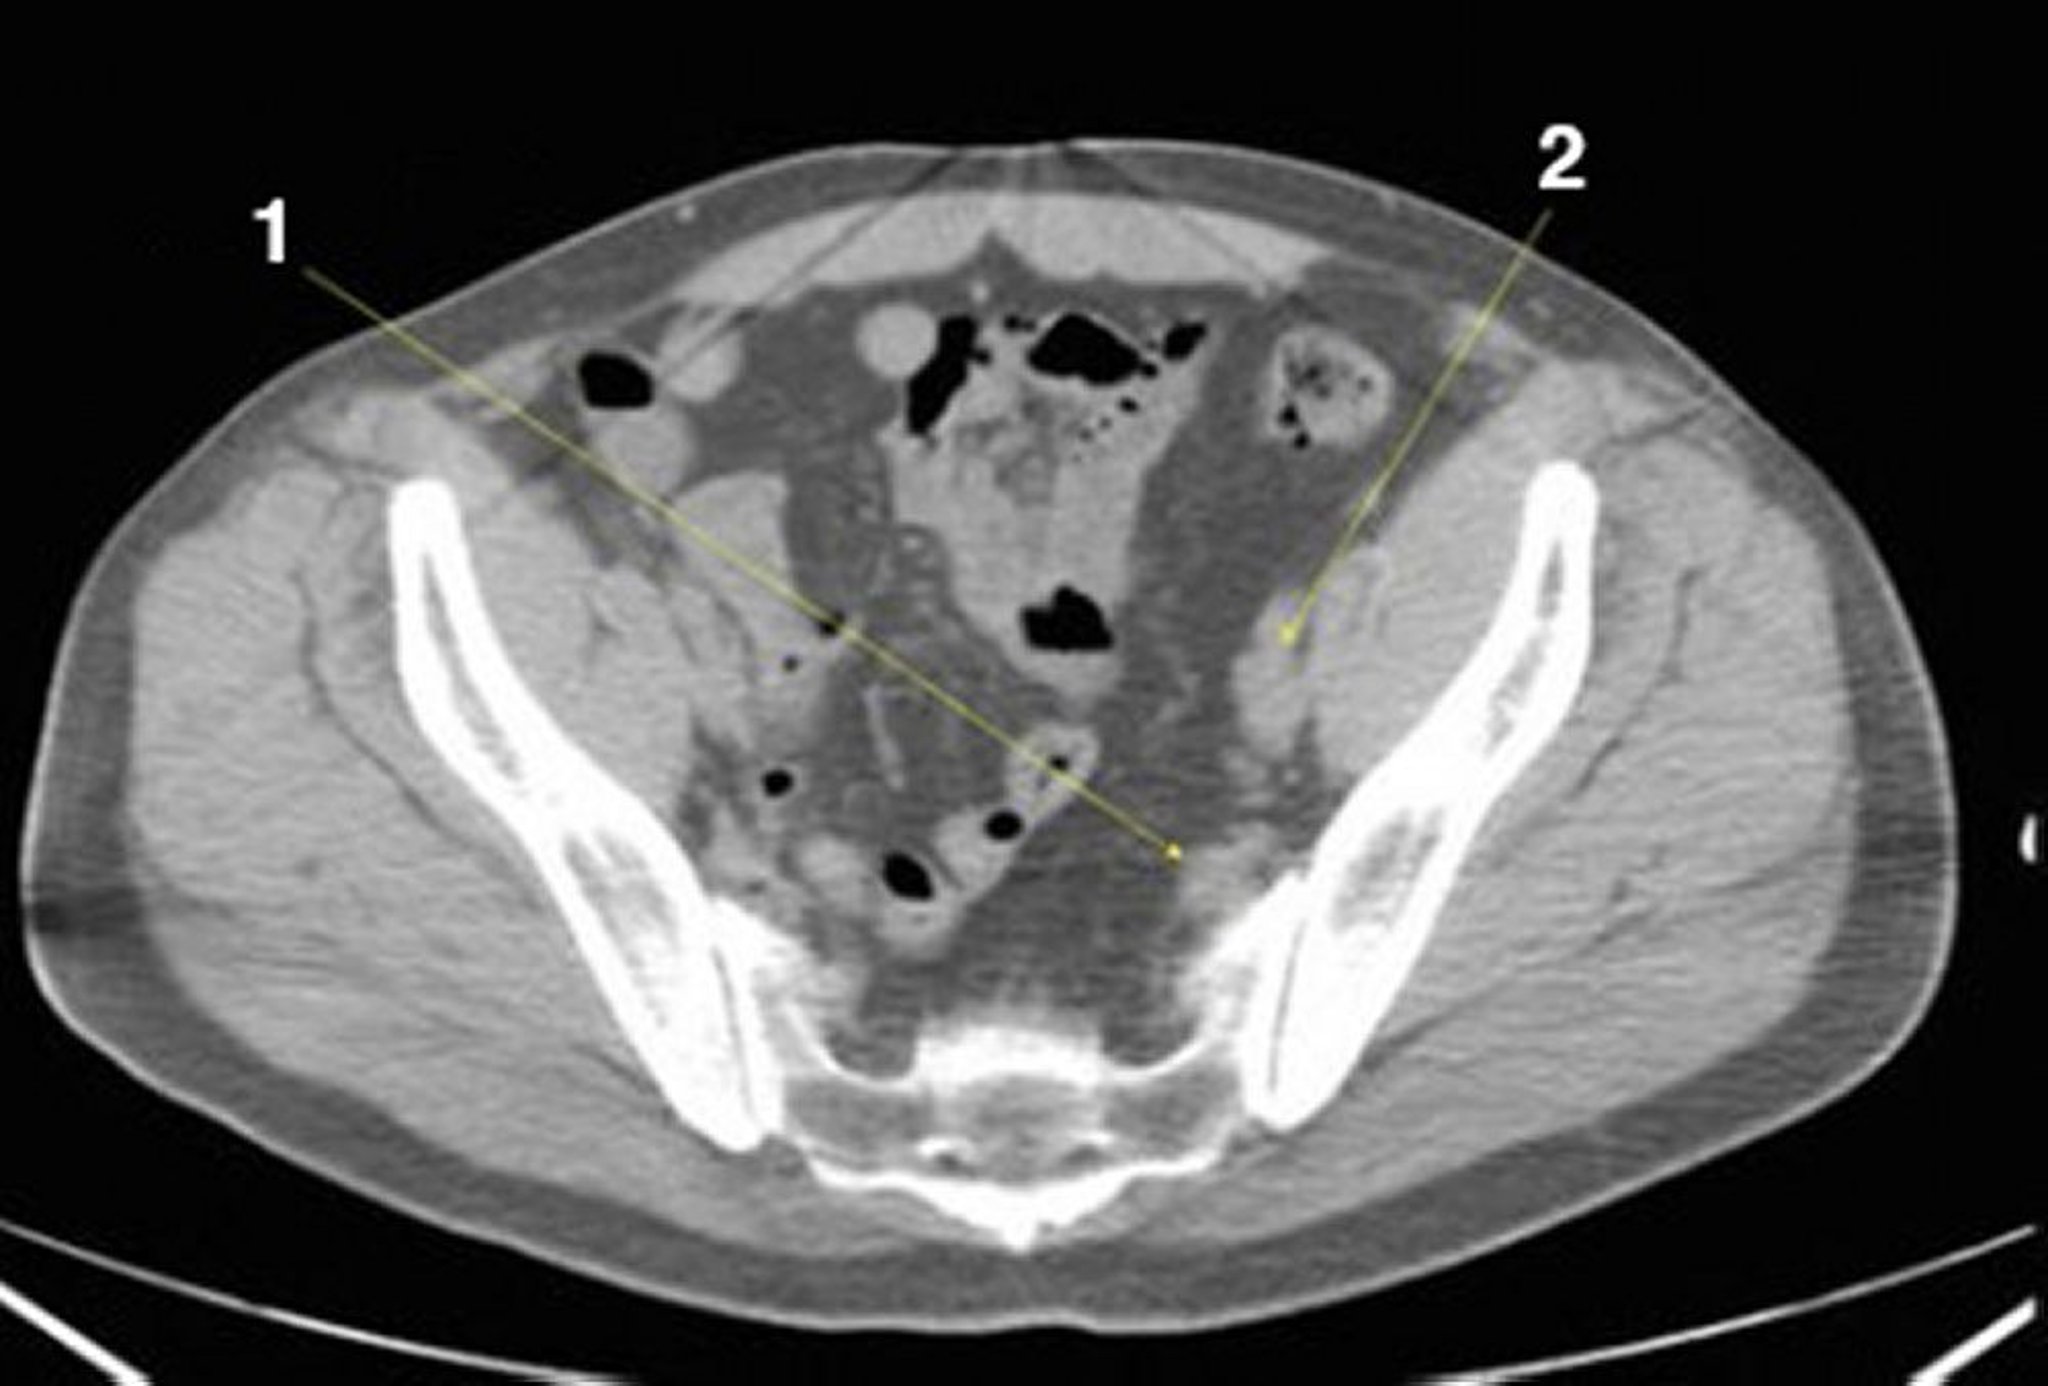

Tomografía computarizada sin contraste de abdomen y pelvis que muestra anatomía normal (corte 24)

1 = vasos ilíacos internos; 2 = vasos ilíacos externos.